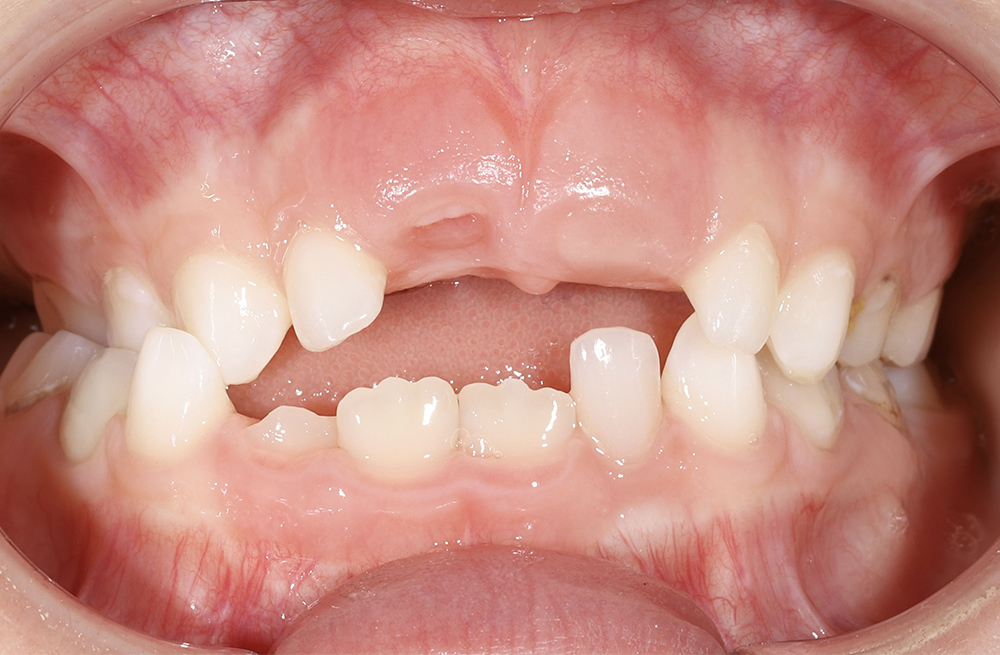

Два этапа ортодонтического лечения у семилетней пациенткиот сложного нарушения прикуса до коррекции положения языка